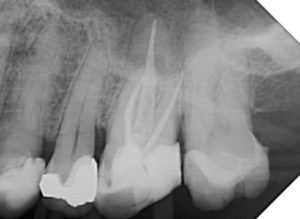

Alguns trabalhos